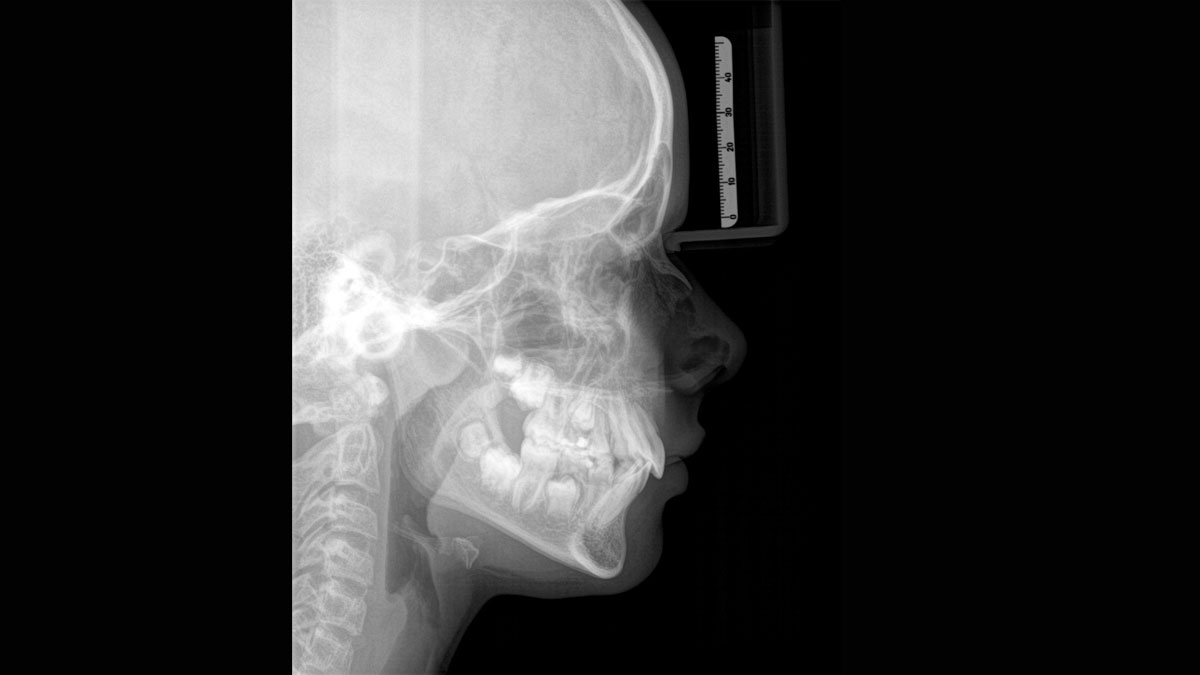

We developed a 10-point concept for easy patient positioning and X-ray imaging. Our concept is primarily about two things: high image quality and comfort for the patient and the assistant. This concept supports and provides the tools needed to ensure high-quality images for treatment analysis and focuses on ergonomics and comfort for the patient and assistant. The patented bite block technology, for example, automatically establishes the correct inclination of the patient's head, positioning the patient in the occlusal plane, partnering with the 3 point head fixation and firm handles to ensure stable positioning-limiting unnecessary correction scans.